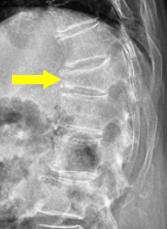

骨粗鬆症性椎体骨折

どんな病気?

せぼね(脊椎)は7個の頚椎、12個の胸椎、5個の腰椎と仙椎から構成されます。腰椎は主に5つの骨と、間にあるクッションのような椎間板、また神経組織が通っている脊柱管から成り立っています。骨粗鬆症性椎体骨折は、骨脆弱性のため脊椎が骨折してしまう病気で、骨粗鬆症のある高齢女性に多く見られます。尻もちなど軽微な転倒で発生することが多いですが、くしゃみ程度でも生じることがあり、約半数ははっきりとした原因が不明なためいつの間にか骨折とも言われています。

症状

腰や背部に痛みが生じます。非常に強い痛みになることもありますが、さほど強い痛みにならない時もあります。骨折すると椎体が変形し脊柱管内に突出すると、神経を圧迫するため下肢(殿部、大腿部、下腿、足など)に放散する痛みやしびれ、足に力が入らない(麻痺)、また排尿や排便に障害(膀胱直腸障害)が出たりすることがあります。

検査方法

骨の脆さを評価するため、骨密度検査を行います。せぼねの変形や椎間板の傷み具合、すべりや不安定性の程度、脊柱管の狭さ、またせぼね全体のバランスなどを見るためにX線検査やCT検査、MRI検査なども行います。進行例では脊柱管の狭さをより詳しく評価するために入院して脊髄造影検査や、同時にどの神経が痛みの原因となっているかを明らかにするために神経の枝に直接麻酔薬を注入する選択的神経根ブロックを行う場合があります。成人期では血管性の下肢の痛みがないか評価するために両手足の血圧を測ることもあります。

治療方法

コルセットや安静、疼痛コントロールなどの保存治療が基本です。3カ月程度で骨癒合(骨がくっつく)し、次第に痛みも改善します。痛みが軽度〜中等度の場合には外来通院が可能です。痛みが強く歩行が困難な場合には、入院治療が必要になることがあります。足の力が入りづらくなったり(麻痺)、排尿や排便に障害(膀胱直腸障害)が出たりした場合、早期離床を目指す場合、あるいは骨折の治りが悪い時には手術治療が考慮されます。低侵襲手術として、つぶれた骨にセメントや人工骨を補填する椎体形成術があります。不十分な場合には、金属性のスクリューなどで脊椎を固定し安定化させる方法もあります。